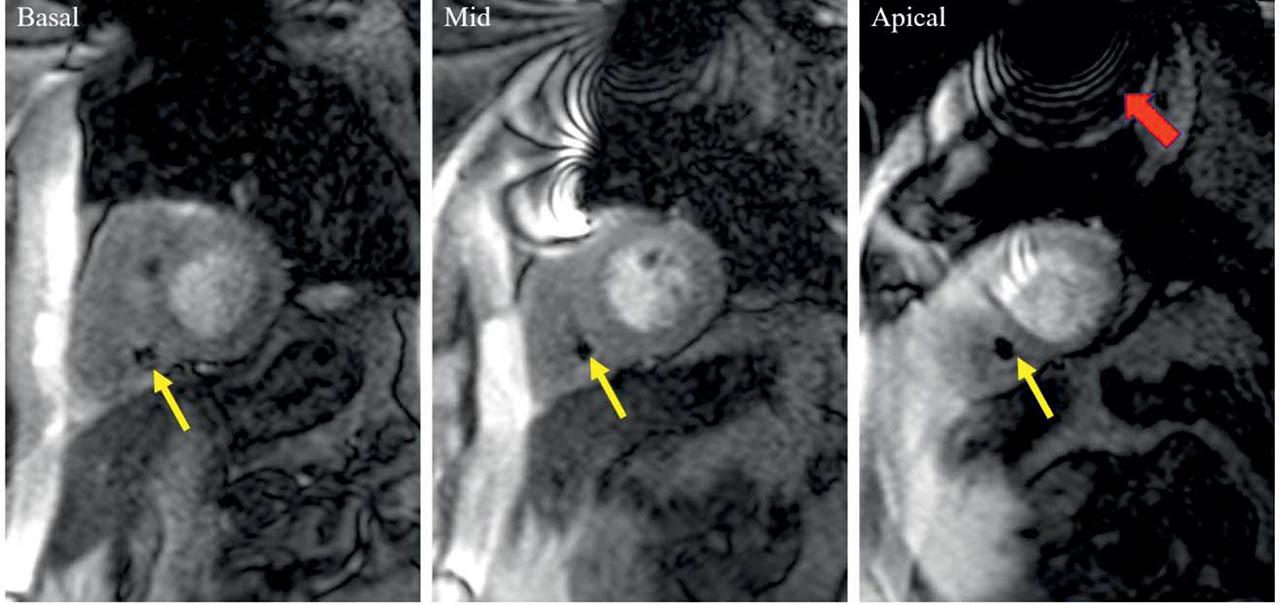

Cardiac implantable electronic devices do not represent nowadays an absolute contraindication for MRI, provided that adequate setting of the device is performed before and after the examination14,15. Moreover, recent technical developments such as wideband myocardial perfusion pulse sequences permit the acquisition of images eliminating most of the significant metallic artifacts that may be associated with intracardiac leads or pulse generator16. In our cohort, one of the patients who underwent stress CMR had a dual chamber pacemaker implanted for intermittent atrio-ventricular block. The images acquired in in this patient had minor artifacts which did not precluded reliable interpretation of perfusion images (Figure 6).

Figure 6

Stress perfusion CMR in a 60-year-old patient with intermediate lesions on invasive coronary angiography, with a dual chamber pacemaker implanted for intermittent AV block. During CMR examination, the pacemaker was set in DOO mode, 80 bpm. Basal, mid and apical short axis slices show the pacemaker right ventricular lead (yellow arrow) which does not induce any metallic artifacts. However, the pulse generator (red arrow), induces a significant artifact which precludes the optimal visualisation of the apical anterior segment only. Overall, the image quality permits reliable interpretation of the stress test.